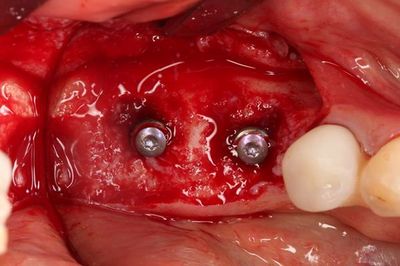

無事に2本のインプラントの埋入を終えました。

トランスファージグを取り外しました。

ヒーリングスクリューH0.5mmでスクリューホールを保護します。